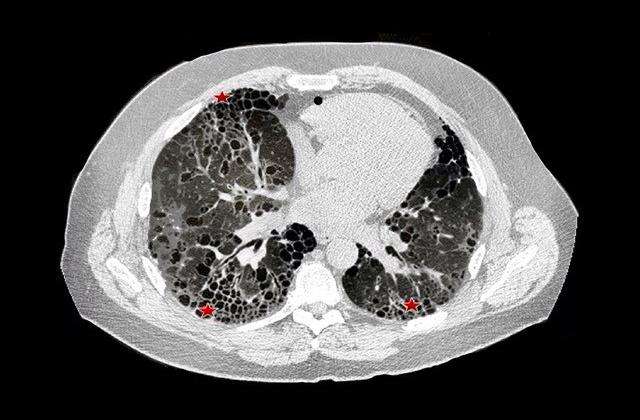

In IPF, normal lung is replaced by scar tissue, a condition called fibrosis. Lungs become stiff, as the disease progresses, and breathing becomes more difficult. Death typically stems from respiratory failure.